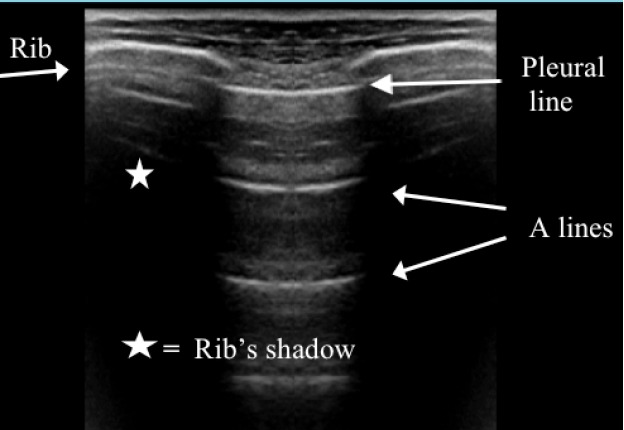

Abstract Image